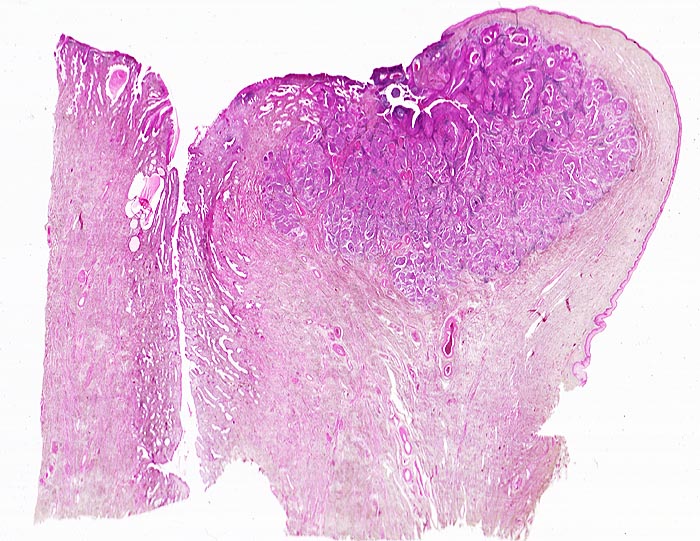

PathoPic – image database / PathoPic ID 4566 - Invasives Plattenepithelkarzinom der Zervix

Invasives Plattenepithelkarzinom der Zervix

Scharf begrenzter, von der vorderen Muttermundslippe im Bereich der Umwandlungszone ausgehender Tumor. Zervikalkanal.

Die Umwandlungszone liegt dort, wo das metaplastische Plattenepithel der Ektozervix die endozervikalen Drüsen überwächst. An dieser Stelle finden sich am häufisten präneoplastische und neoplastische Veränderungen des Zervixepithels.